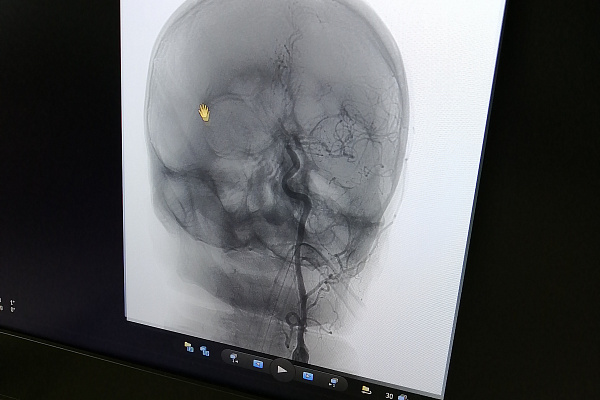

-К шейному и внутричерепному сосудам достаточно было одного доступа – через бедренную артерию. Сначала работали со стенозом - он затруднял доступ к аневризме, расположенной выше по кровотоку. Стентирование сонной артерии само по себе непростое вмешательство с использованием большого набора инструментов. Например, здесь необходимо устанавливать так называемые ловушки для тромбов, чтобы исключить их попадание в кровоток. Сложность в лечении аневризмы была связана как с её размерами – всего 3 миллиметра в диаметре, так и дистальным расположением – дальше «Виллизиева круга». При этом у неё оказалась достаточно широкая шейка, которая не смогла бы удержать микроспираль – специальную мягкую проволоку для заполнения мешка аневризмы и предотвращения дальнейшего поступления туда крови. Пришлось применить особую ассистирующую, то есть вспомогательную методику – с использованием специального микробаллона. В общей сложности операция заняла 2 часа 10 минут, - рассказывает рентгенохирург Екатерина Иванкова.